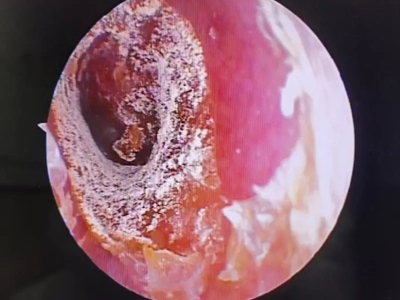

外耳道

脱屑 · 化脓

霉菌性外耳道炎耳朵里有脓性分泌物图

霉菌性外耳道炎患者的外耳道处有大量黄白色脓液性分泌物,团块状附着于外耳道壁上,边缘有碎纸样白色鳞屑,耳朵内部黏液呈灰黑色,伴瘙痒感。